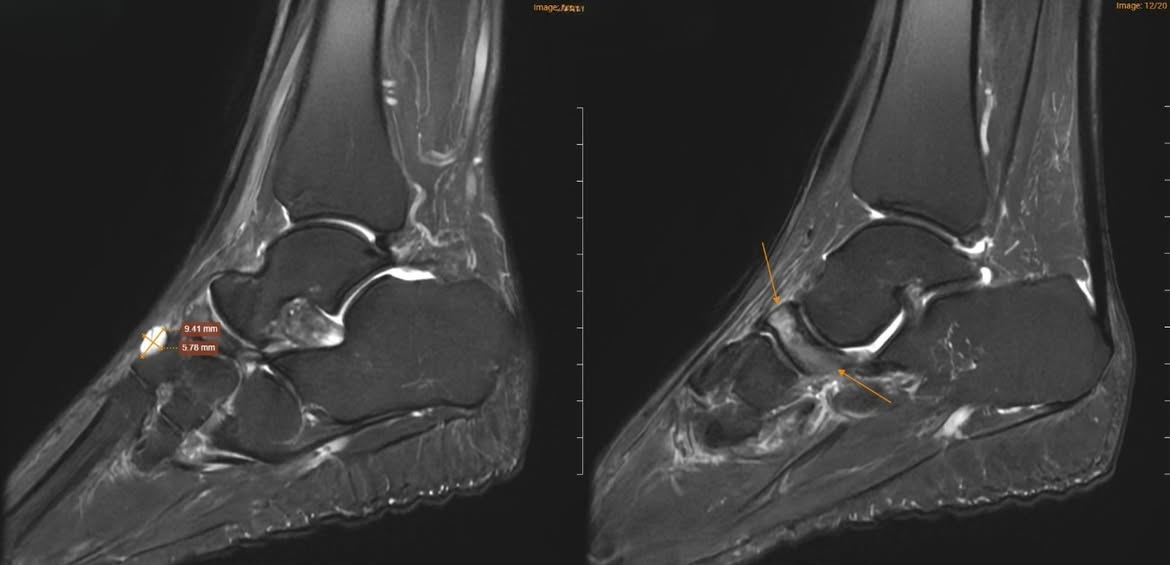

Để xác định nguyên nhân, các bác sĩ đã chỉ định chụp cộng hưởng từ (MRI). Kết quả cho thấy xương ghe bị xẹp và biến dạng điển hình hình “dấu phẩy”, kèm đặc xương dưới sụn và phù tủy xương rõ rệt. Ngoài ra, nhiều tổn thương phối hợp cũng được ghi nhận như gai xương, phù dây chằng, tràn dịch khớp cổ chân.

Dựa trên lâm sàng và hình ảnh học, bệnh nhân được chẩn đoán theo dõi Hội chứng Mueller-Weiss ở chân phải và phù tủy xương sên trái.